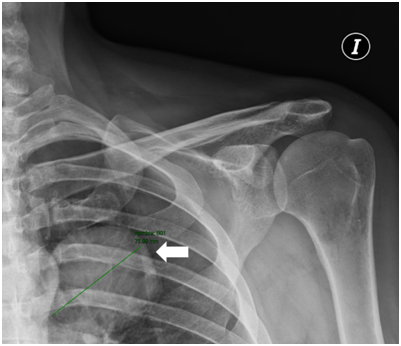

The patient consulted with a cardiology team where an electrocardiogram and an exercise test were performed, being reported normal. He was then referred to the orthopedics service due to shoulder pain persistence. A shoulder x-ray showed a tumor in the left thorax measuring 78.99mm in diameter (Figure 1). In follow up studies, a left humeral lesion of neoplastic appearance was revealed. In the magnetic resonance an intramedullary lesion is reported in the sternum, incidentally, a solid mass is observed in the left lung, it also shows tendinitis of the rotator cuff and subacromial impingement (Figures 2-4). Therefore, it is decided to perform a Computed Tomography scan which reported atelectasis mainly in the left upper lobe and a tumor measuring 65mm (Figure 5). The Positron Emission Tomography - Computed Tomography scan result was an increase of the metabolism by neoplastic activity, lymphadenopathy and bone lesions, hepatosplenomegaly and non- specific alterations in the colon (Figure 6).

Figure 1 Shoulder x-ray showed a tumor in the left thorax measuring 78.99mm in diameter.